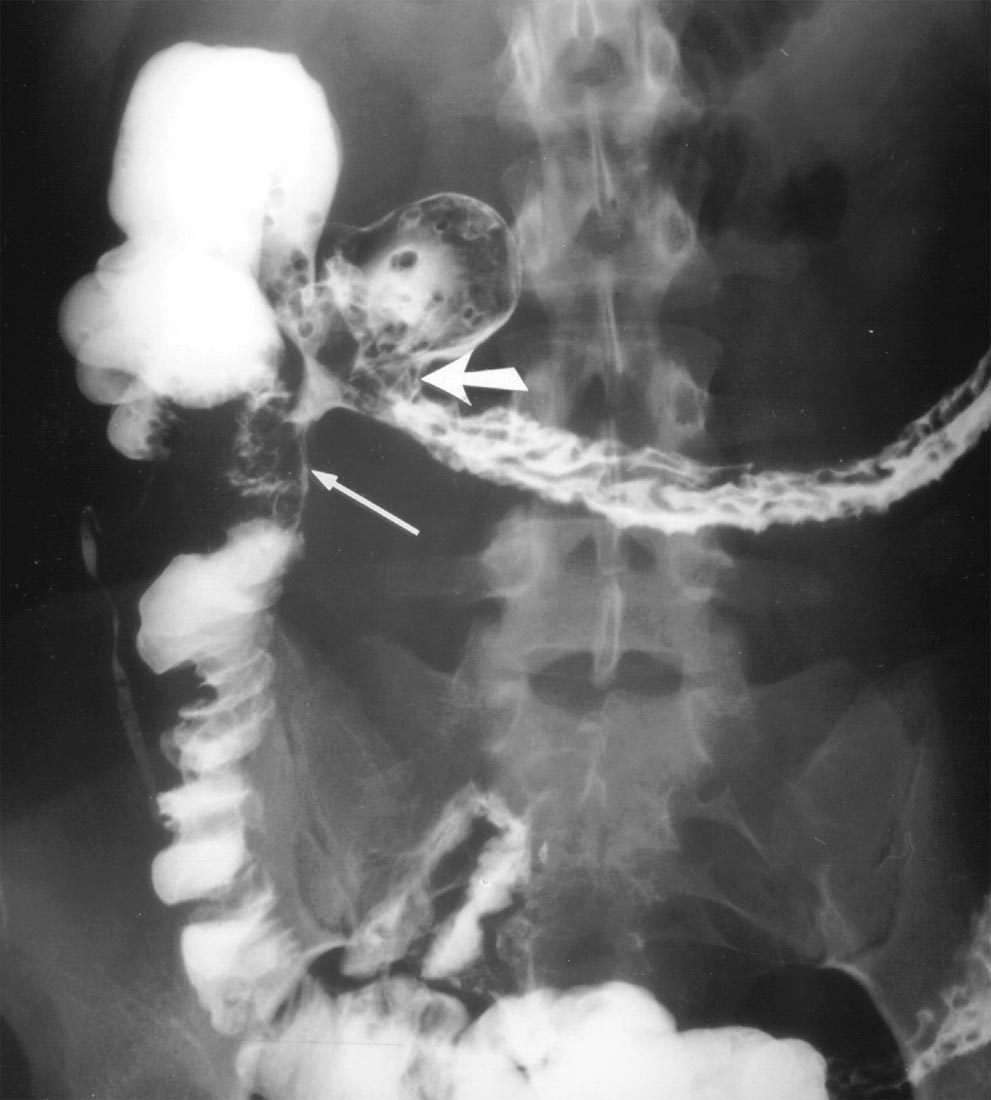

From www.researchgate.net

Barium Xray Postoperative barium swallow, demonstrating the colonic Is Barium X Ray Dangerous The risks of a barium swallow test may include problems from radiation exposure, birth defects and intestinal issues. Why you might have it. Barium passes through the digestive system and does not cause a person any harm. As it passes through the body,. You may want to ask your healthcare provider about the amount of radiation used during the swallowing. Is Barium X Ray Dangerous.